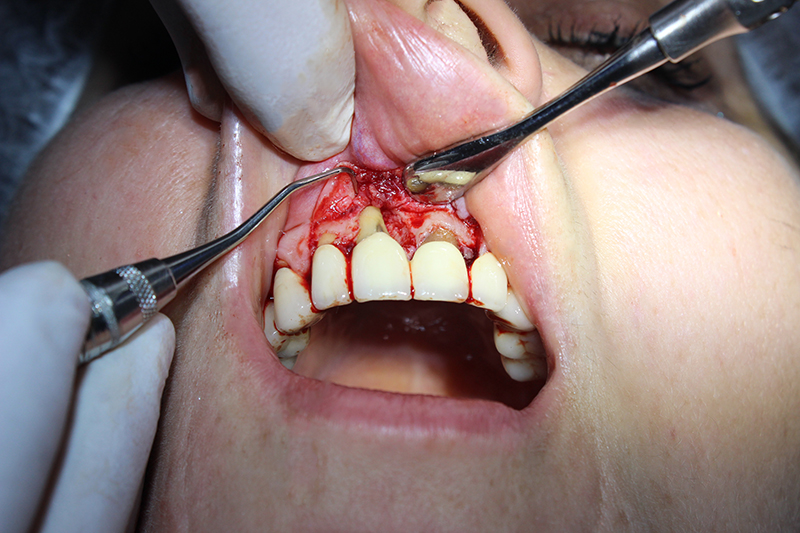

В медиальной области 11-го зуба пациентки была резорбция кости. Для лечения была проведена пародонтальная операция:

1.сглаживание поверхности корня;

2.добавление костной ткани;

3.установка мембраны.